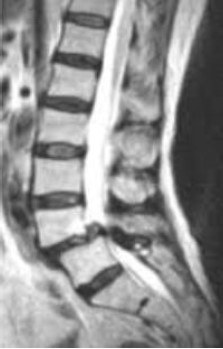

Sobre o diagnóstico evidenciado na ressonância abaixo são feitas três afirmativas.

I. L4-L5 é o nível mais frequentemente acometido por essa patologia.

II. O subtipo ístmico ocorre devido a defeitos nas pars interarticulares, sejam eles fraturas agudas ou crônicas, resultantes de traumas repetitivos.

III. Cirurgia está indicada para os casos em que há mielopatia, radiculopatia ou claudicação neurogênica. Contudo, tratamento conservador pode ser adequado para os casos em que não há bordas escleróticas, mas há sinais de atividade inflamatória nos exames de imagem.